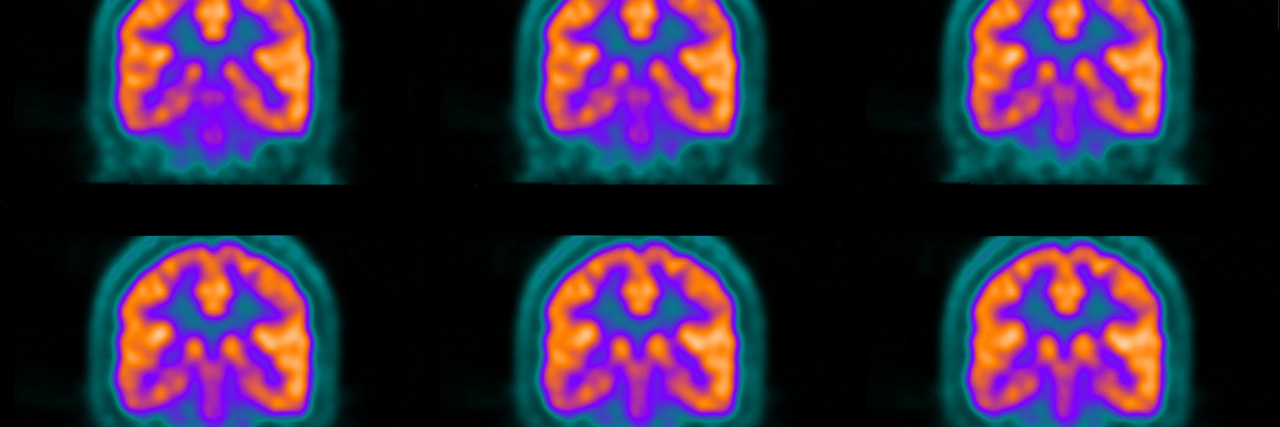

Although it’s been suggested that neuroinflammation plays a role in fibromyalgia, this is the first study to look at brain glial activation in fibro patients. In the positron emission tomography (PET) study, researchers looked at the translocator protein (TSPO), a protein that increases in response to activated glial cells (specifically microglia and astrocytes). They measured the levels of TSPO binding in 31 patients with fibromyalgia and 27 healthy controls to determine if glial activation plays a role in fibromyalgia.

Researchers found that TSPO binding levels were indeed higher in patients with fibromyalgia than those without. While increased glial activation may be an indicator of chronic pain in those with fibro, researchers also found a correlation between the elevated TSPO levels and the participants’ subjective reporting of fatigue. This suggests that glial activation may play a role in the pathology of both pain and fatigue.